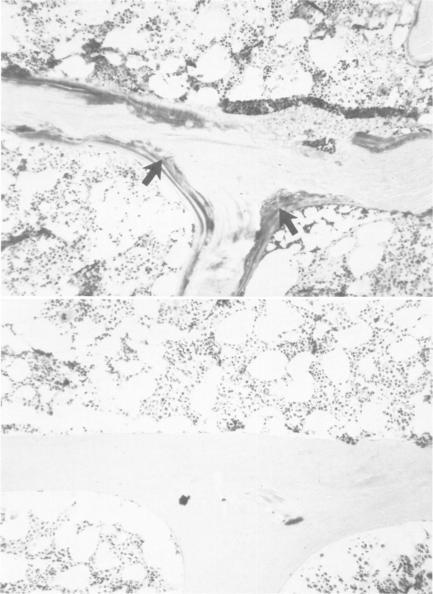

Jejunoileal bypass surgery is fraught with many longterm complications, among which is hypovitaminosis D. The relationship, if any, of hypovitaminosis D to the skeletal disease which may occur following this operation is, however, unknown. Consequently, we studied eight patients with low circulating levels of 25-hydroxyvitamin D who had undergone jejunoileal bypass at least two and one-half years previously. Despite the absence of skeletal symptoms, the bone biopsies of six of these patients were abnormal. The volume of trabecular bone was diminished in the group as a whole, and half the patients had an excess of unmineralized skeletal matrix. However, no noninvasive diagnostic technique identified those patients with skeletal disease. We therefore conclude that recognition of those jejunoileal bypass patients potentially at risk to develop clinically significant bone disease requires biopsy of the skeleton.

空肠回肠旁路手术充满了许多长期并发症,其中维生素D缺乏症就是其一。然而,维生素D缺乏症与该手术后可能发生的骨骼疾病之间(若存在关联的话)的关系尚不清楚。因此,我们研究了8例25-羟维生素D循环水平较低的患者,这些患者至少在两年半之前接受了空肠回肠旁路手术。尽管这些患者没有骨骼症状,但其中6例患者的骨活检结果异常。总体而言,该组患者的小梁骨体积减少,半数患者存在未矿化骨骼基质过多的情况。然而,没有任何非侵入性诊断技术能够识别出那些患有骨骼疾病的患者。因此,我们得出结论,要识别那些空肠回肠旁路手术后有潜在风险发展为具有临床意义的骨病的患者,需要进行骨骼活检。